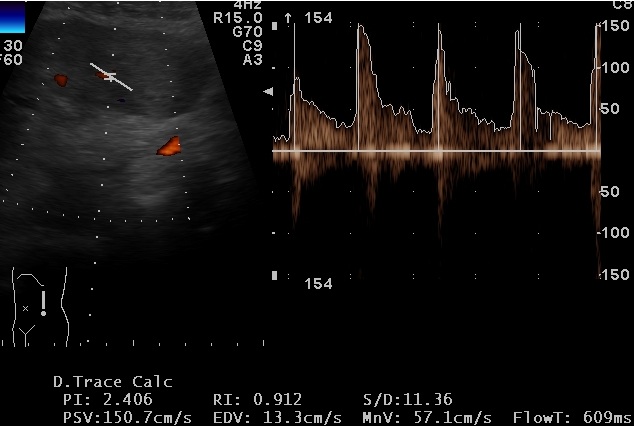

Figure 4: Splenic vascular resistive index |

Also the analysis of color Doppler signal is not characterizing. The sonographic appearance of LCA depends on the type and number of tumor vessels [8]. Even by CT scan, LCA is often indistinguishable from lymphomas, metastatic disease and hemangiomas [9].